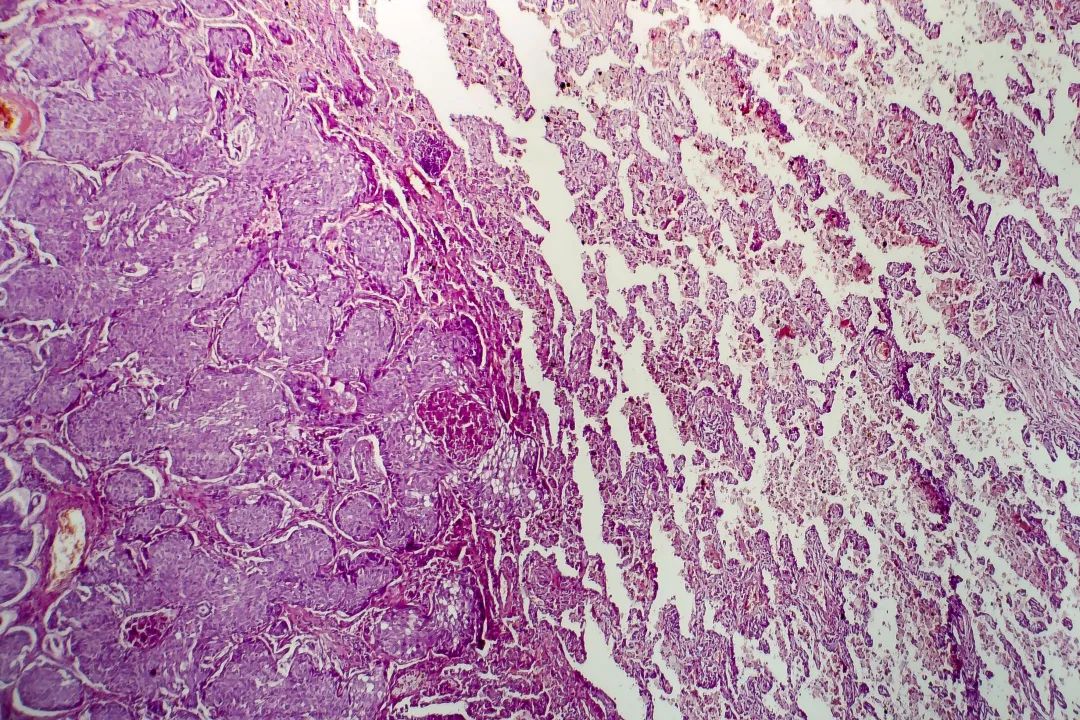

CT

肺腺癌在光学显微镜下的照片